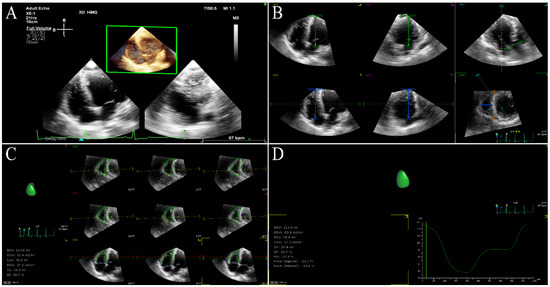

6.1. Left Ventricular Global Systolic Function